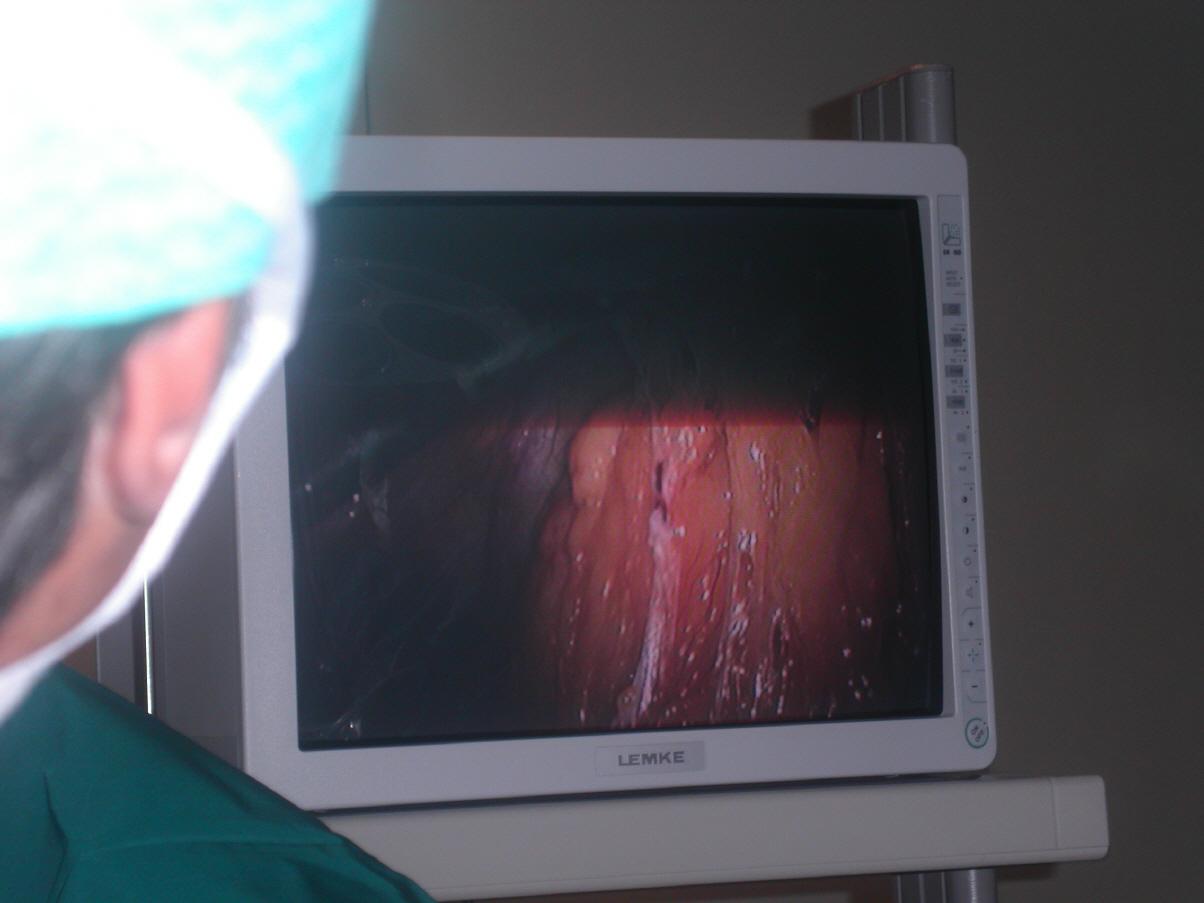

Große Erfahrung habe ich auf dem Gebiet der "Schlüssellochchirurgie" (Laparoskopie) und der Hysteroskopie (Chirurgie unter Sicht zur Entfernung von Schleimhautkrebs, Myomen und Polypen) Inkontinenzchirurgie, Band-OP bis TVT.